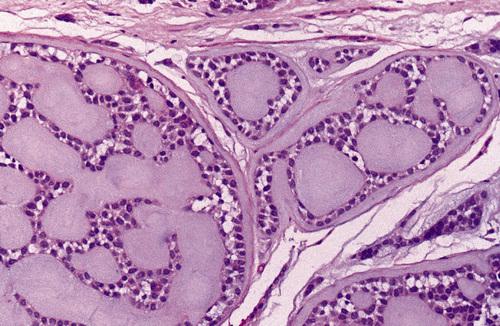

Low-power view showing a papillary cystic tumor with a lymphoid stroma. The epithelium is oncocytic, forming uniform rows of cells surrounding cystic spaces.

Warthin tumor

High-power view of epithelial lining showing double row of oncocytes with adjacent lymphoid stroma. The inner luminal layer consists of tall columnar cells with centrally placed, palisaded, and slightly hyperchromatic nuclei. Beneath this is a second layer of cuboidal or polygonal cells with more vesicular nuclei.

Warthin tumor